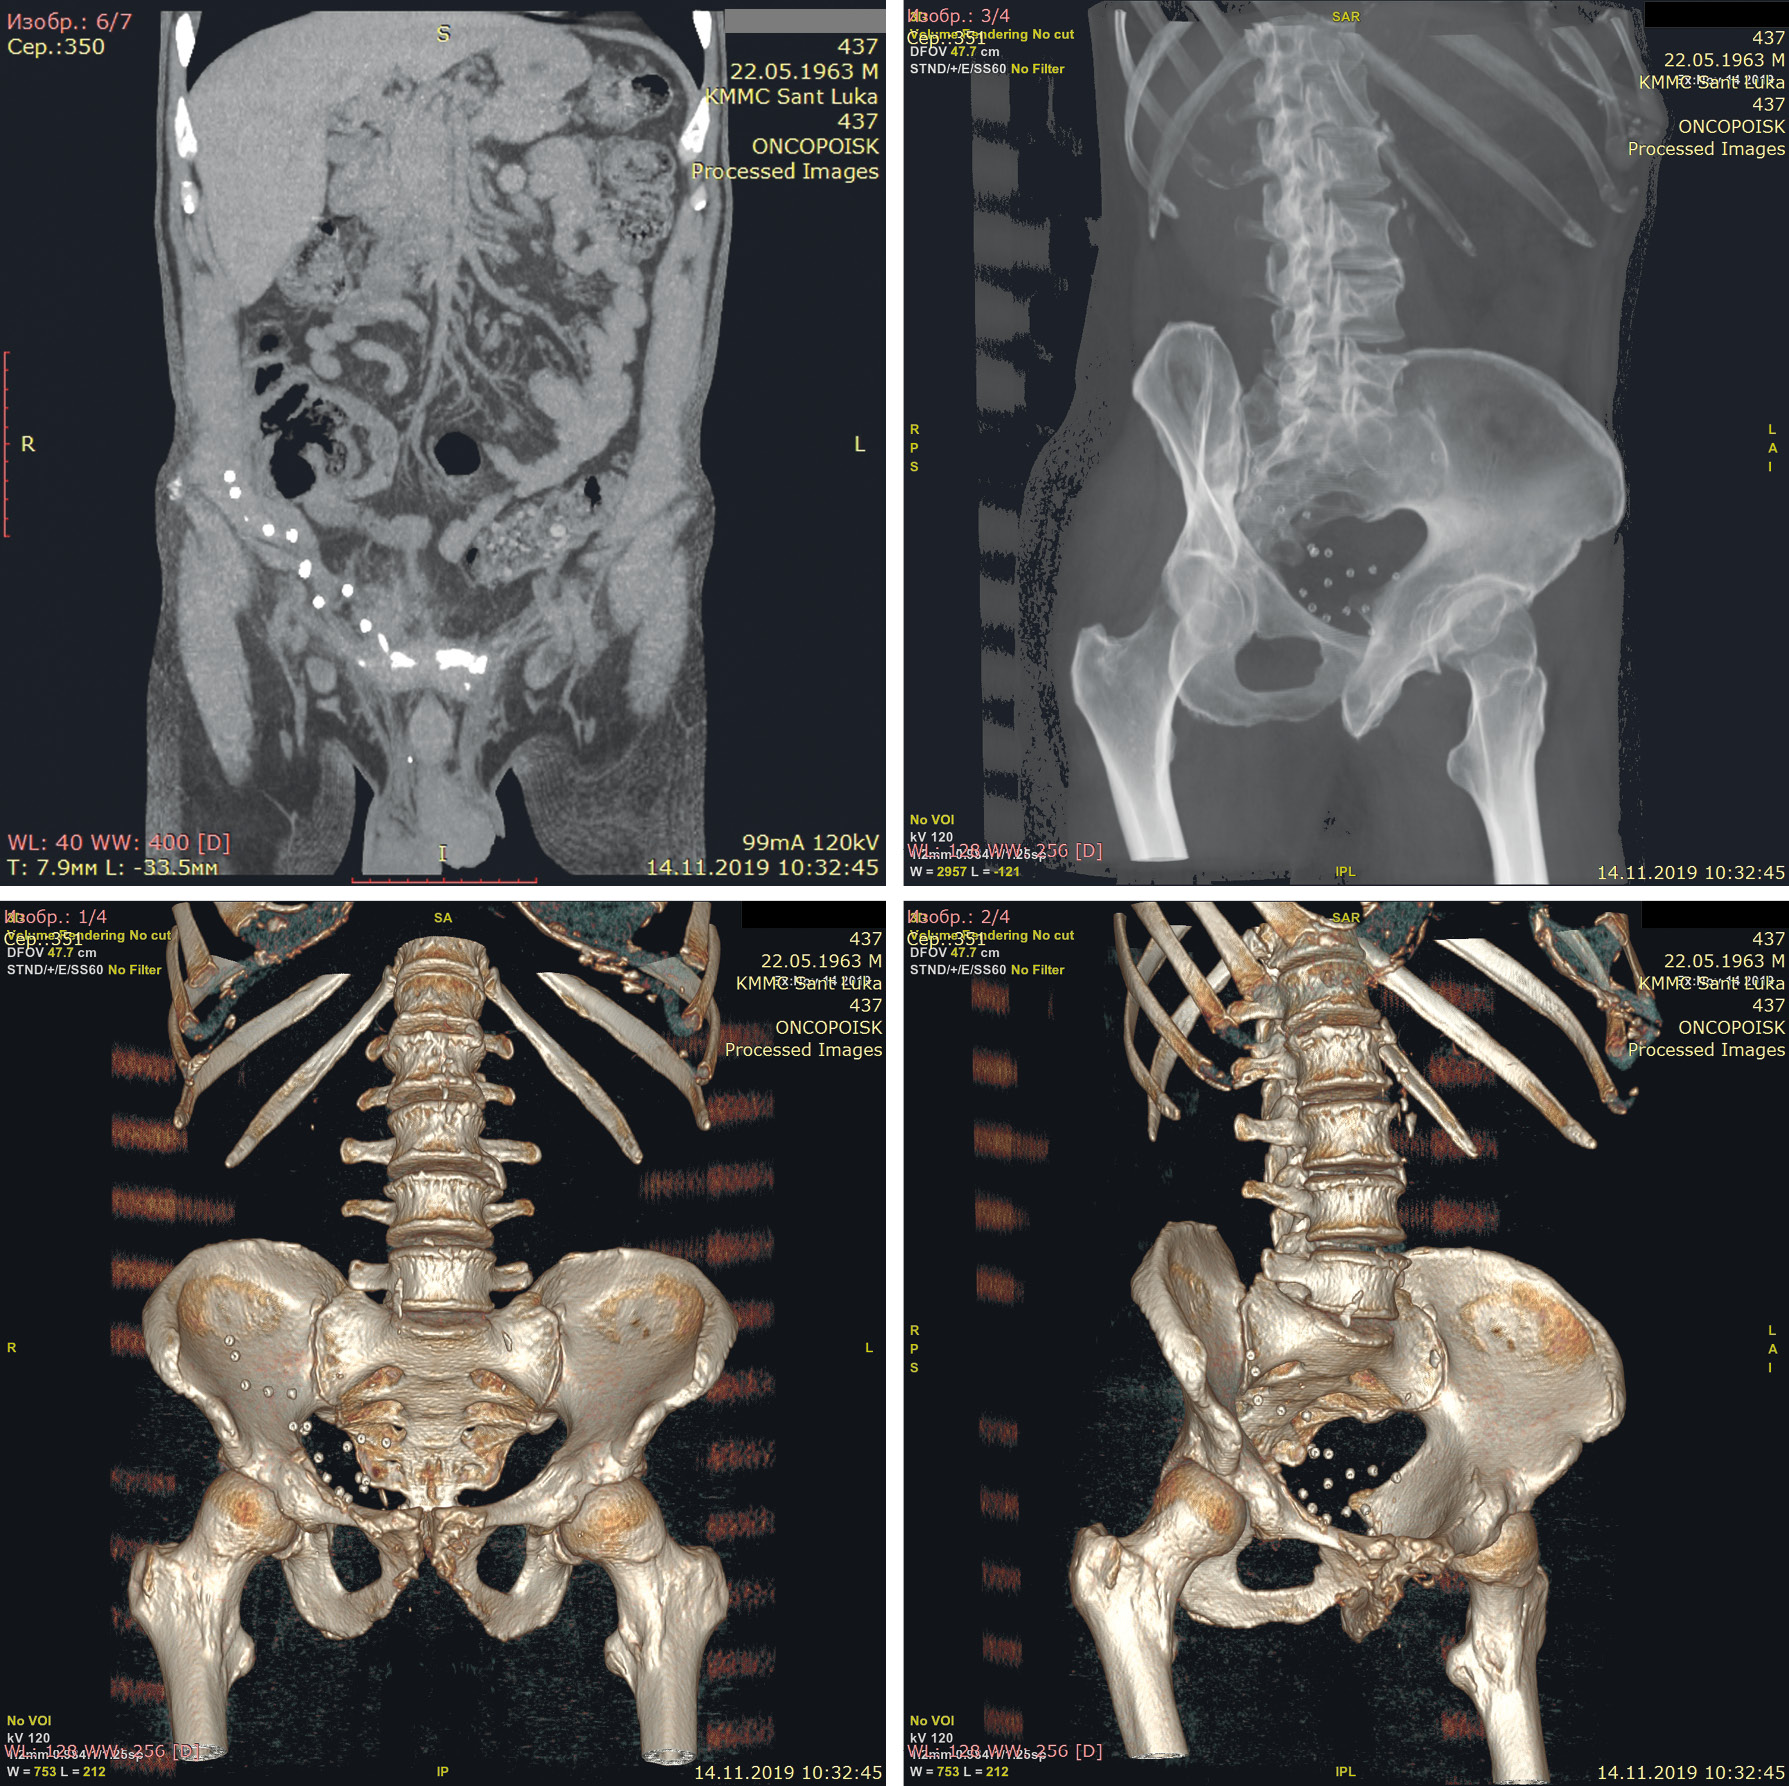

Оперативное вмешательство

Выполнен послойный доступ параректальным разрезом в брюшную полость, визуализирован сетчатый протез с множественными такерами. Такеры зажимом Бильрот выкручены с подлежащих тканей (общее количество 22) (рис. 2), иссечен сетчатый имплантат (рис. 3), брюшная полость дренирована, послойно ушита.

Рис. 2. Пациент С., 52 года: удаление титановых такеров и сетчатого имплантата

Рис. 3. Удаленный сетчатый протез и такеры

Послеоперационный период протекал без осложнений, в первые сутки пациент отмечал исчезновение предоперационных жалоб. К концу выписки полностью физически реабилитирован, в заинтересованных областях отмечаются остаточные явления парестезии. Выписан из отделения в удовлетворительном состоянии, даны рекомендации невропатолога. В телефонном режиме через 3 мес после операции жалоб не предъявляет, устроился на работу.